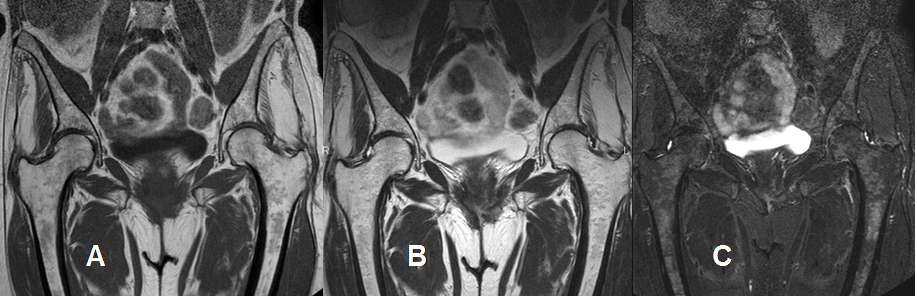

Fig 194. Mieloma.

A: RM coronal en T1, B: RM coronal en T2 y C: RM coronal en STIR. Patrón parcheado en los huesos fémur e iliaco, hipointenso en T1 y T2 e hiperintenso en STIR, por mieloma.